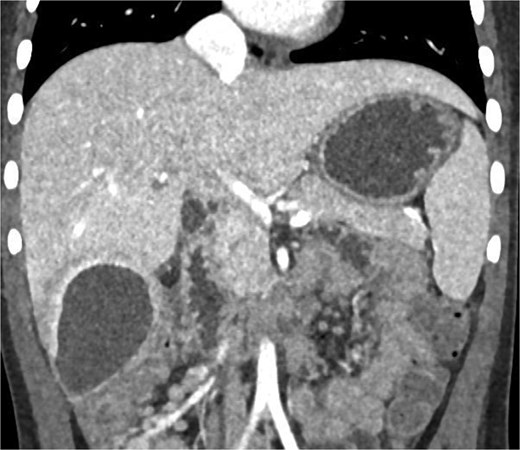

CT imaging of the abdomen (Fig. 2) revealed a retrocecal appendix in its typical location, measuring 50 mm in length and 14 mm in diameter, with a thickened wall (5.5 mm). A proximal fecalith measuring 3 × 3 × 14 mm was identified. Post-contrast enhancement of the appendix wall was noted. Adjacent to segments V and VI of the liver, a fluid collection with an air-fluid level was observed, measuring 5.3 × 3.8 × 4.5 cm, surrounded by a 3 mm enhancing capsule, consistent with a hepatic abscess. A second, smaller hypodense collection measuring 13 × 22 × 11 mm was found inferior to the primary abscess. Additional findings included reactive lymphadenopathy (up to 8 × 4 mm) and free fluid in the right iliac fossa (up to 12 mm). Other abdominal organs, including the liver, pancreas, kidneys, and spleen, appeared normal. The findings were consistent with complicated acute appendicitis and associated abscesses.

CT imaging of acute appendicitis with fecalith and multiple hepatic abscesses.

Imaging plays a crucial role in diagnosing appendicitis and its complications. Ultrasound is often the initial modality used, but it may have limited sensitivity in detecting intra-abdominal abscesses, particularly when the appendix is not visualized or when findings are inconclusive [4, 5]. In such cases, contrast-enhanced CT is considered the gold standard, providing detailed visualization of the appendix and associated complications, including abscess formation [2, 4]. In the present case, the initial ultrasound findings suggested an atypical position of the appendix and a pathological fluid collection, but CT imaging confirmed a retrocecal appendix and subhepatic abscesses (Figs 4 and 5), guiding appropriate management.

CT axial view of a subhepatic abscess. Contrast-enhanced capsule and fluid-air level visible.